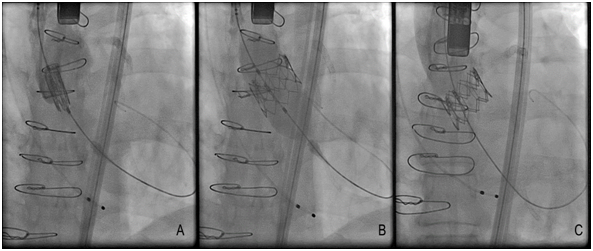

There are several approaches to transcatheter aortic valve replacement which include transfemoral, transapical, transaxillary, transubclavian, transcarotid, transcaval, and transaortic. The most common approach is transfemoral (Figure 1) and it appears to be safer in observational analyses than alternative access.18 An important determinant for transfemoral access is size of the iliofemoral circulation and its trajectory, as measured on a pre-operative CT scan. Patients with smaller iliofemoral vessels can develop more vascular complications.19 There is a trend, in selected cases and using transfemoral access, to perform the procedure without general anesthesia, intubation and surgery dissection. If patients do not have suitable vascular anatomy for transfemoral access, then an alternative approach can be undertaken in hybrid cardiovascular suites, which allow for integration of interventional cardiology and cardiac surgical techniques. The transfemoral vascular access for TAVR is the best choice for the procedure and improves the patient’s functional recovery.20 The size reduction of the delivery catheter of several TAVR systems has therefore increased the proportion of patients suitable for the transfemoral approach. For example, The Core Valve Evolutes R (23, 26, 29 mm; Medtronic, Dublin, Ireland) and SAPIEN 3 (23, 26 mm; Edwards Life sciences, Irvine, CA, USA) can be implanted using 14 Fr Inline sheath (Medtronic) or expandable-sheath technology, respectively. These simple systems can facilitate transfemoral TAVR in vessels as small as 5.5 mm (SAPIEN 3) or even 5.0mm (Evolut R).

Until this moment, the TAVR devices approved and non-approved are described in (Table 1), and some TAVR devices have their fluoroscopic view demonstrated in (Figure 2). There was a recent report about Lotus valves recall due to pin troubles, following reports of problems with the device’s locking mechanism. The problem, according to the company, is the premature release of a pin connecting the Lotus valve to the device’s delivery system. Boston Scientific expects to reintroduce the Lotus to Europe and other regions in the fourth quarter of this year (2017).20 The most patients considered for TAVR undergo multimodal imaging assessment of the aortic root. The multislice computed tomography and/or three-dimensional echocardiography are the imaging modalities of choice (according to availability and local expertise) to evaluate the annular dimensions (diameters, area, perimeter) and unique anatomical features of each patient. A variety of adverse anatomical features may complicate TAVR procedure, and in such cases the availability of multiple TAVR technologies can facilitate the procedure safety.21